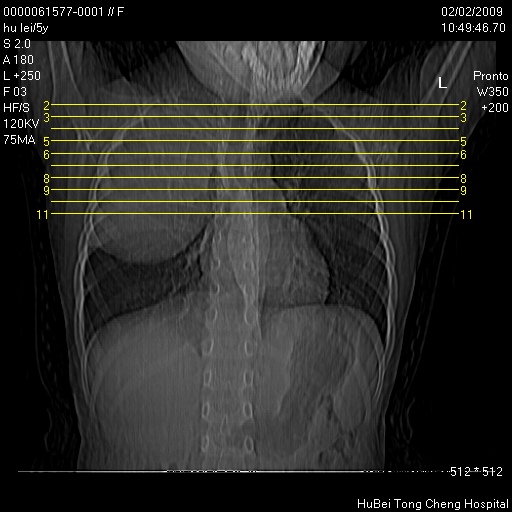

标题: PED1732:M5Y,右肺囊性占位!

患者:男,5。无明显不适,拍胸片考虑右肺囊肿。

行ct扫描,图象如下: